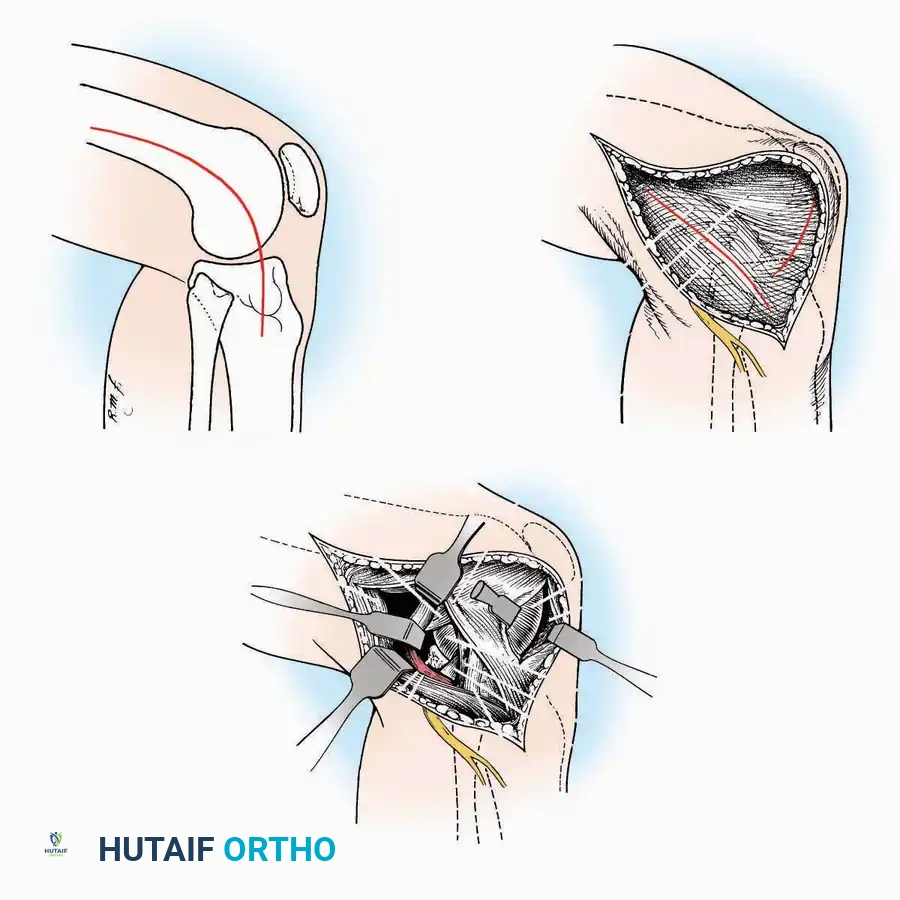

Kocher Approach (Curved L)

Indications: Complete excision of the calcaneus (calcanectomy) for malignant tumors or recalcitrant osteomyelitis.

Surgical Technique:

* Incision: Incise the skin over the medial border of the Achilles tendon, starting 7.5 cm proximal to the calcaneal tuberosity. Extend it distally to the inferoposterior aspect of the tuberosity, curve it transversely around the posterior heel, and continue distally along the lateral surface of the foot to the tuberosity of the fifth metatarsal.

* Deep Dissection: Divide the Achilles tendon directly at its insertion and carry the dissection down to the bone.

* Enucleation: To reach the superior surface, free all tissues beneath the severed Achilles tendon. The calcaneus can then be enucleated subperiosteally or extraperiosteally depending on the oncologic or infectious margins required.